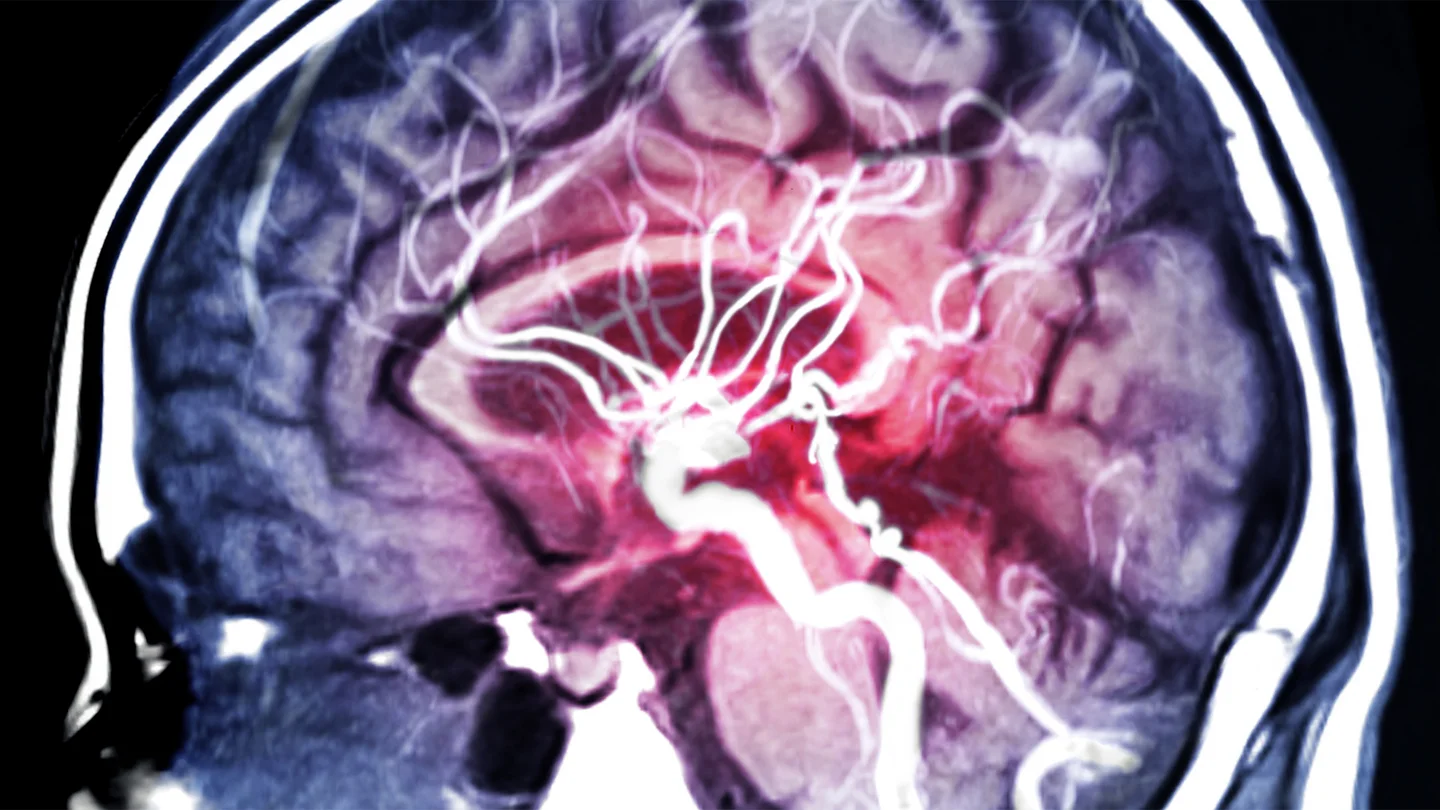

Was ist ein Hirnaneurysma?

Bei einem Aneurysma handelt es sich um die sack- oder beerenförmige Ausbuchtung einer Schlagader (Arterie). Dazu kommt es, wenn die Gefäßwand an einer Stelle nicht mehr fest und elastisch ist und sich dadurch nach außen wölbt.

Aneurysmen können an verschiedenen Arterien entstehen, beispielsweise an der Hauptschlagader im Bauch. Befindet sich die Wölbung an einer Schlagader des Gehirns, spricht man von einem Hirnaneurysma oder Hirnarterienaneurysma. Häufig bilden sich solche Aneurysmen an Verzweigungsstellen der Arterien, über die das Gehirn mit Blut versorgt wird. Wenn ein Hirnaneurysma reißt, kommt es zu einer lebensbedrohlichen Hirnblutung.

Wie stellt man ein Hirnaneurysma fest?

Bei häufigen Kopfschmerzen oder Sehstörungen kann man mit einer Magnetresonanztomographie (MRT) oder eine Computertomographie (CT) die Ursache für die Beschwerden ermitteln.

Mit einer digitalen Subtraktionsangiographie (DSA) lassen sich Aneurysmen besonders gut sichtbar machen: Dabei wird eine Röntgenaufnahme mit und eine Aufnahme ohne Kontrastmittel gemacht. Daraus kann der Computer anschließend ein Bild errechnen, auf dem nur noch die Blutgefäße zu sehen sind.